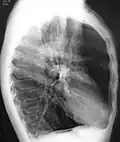

A chest X-ray is not useful to establish a diagnosis of COPD, but it is of use in either excluding other conditions or including comorbidities such as pulmonary fibrosis and bronchiectasis. Characteristic signs of COPD on X-ray include hyperinflation (shown by a flattened diaphragm and an increased retrosternal air space) and lung hyperlucency.[5] A saber-sheath trachea may also be shown that is indicative of COPD.[111]

A CT scan is not routinely used except for the exclusion of bronchiectasis.[5] Pulse oximetry measurement of peripheral oxygen saturation is recommended in people with clinical signs of respiratory failure or right heart failure.[5] An analysis of arterial blood is recommended in those with a peripheral oxygen saturation of 92% or less to determine actual blood oxygen level and assess for high levels of carbon dioxide in the blood, which may have therapeutic implications such as need for non-invasive ventilation or oxygen supplementation.[10] WHO recommends that all those diagnosed with COPD be screened for alpha-1 antitrypsin deficiency.[40]